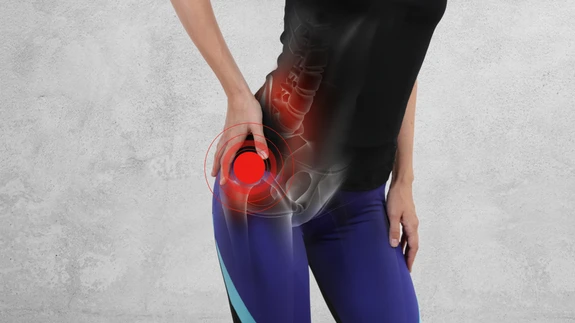

Valuvaba elu vahetatud puusaliigesega

Puusaliigese asendamist tehisliigese ehk endoproteesiga on vaja juhul, kui kulunud või kahjustunud liiges põhjustab ravimitele allumatut valu ja selle liikuvus on piiratud, et taastada jala normaalne ...

Kunstliigest ei maksa karta

Kunstliiges on mõnikord ainus vahend, mis laseb jälle valuta ja liikudes edasi elada....

Kulunud liiges kulumatu vastu, 2. osa